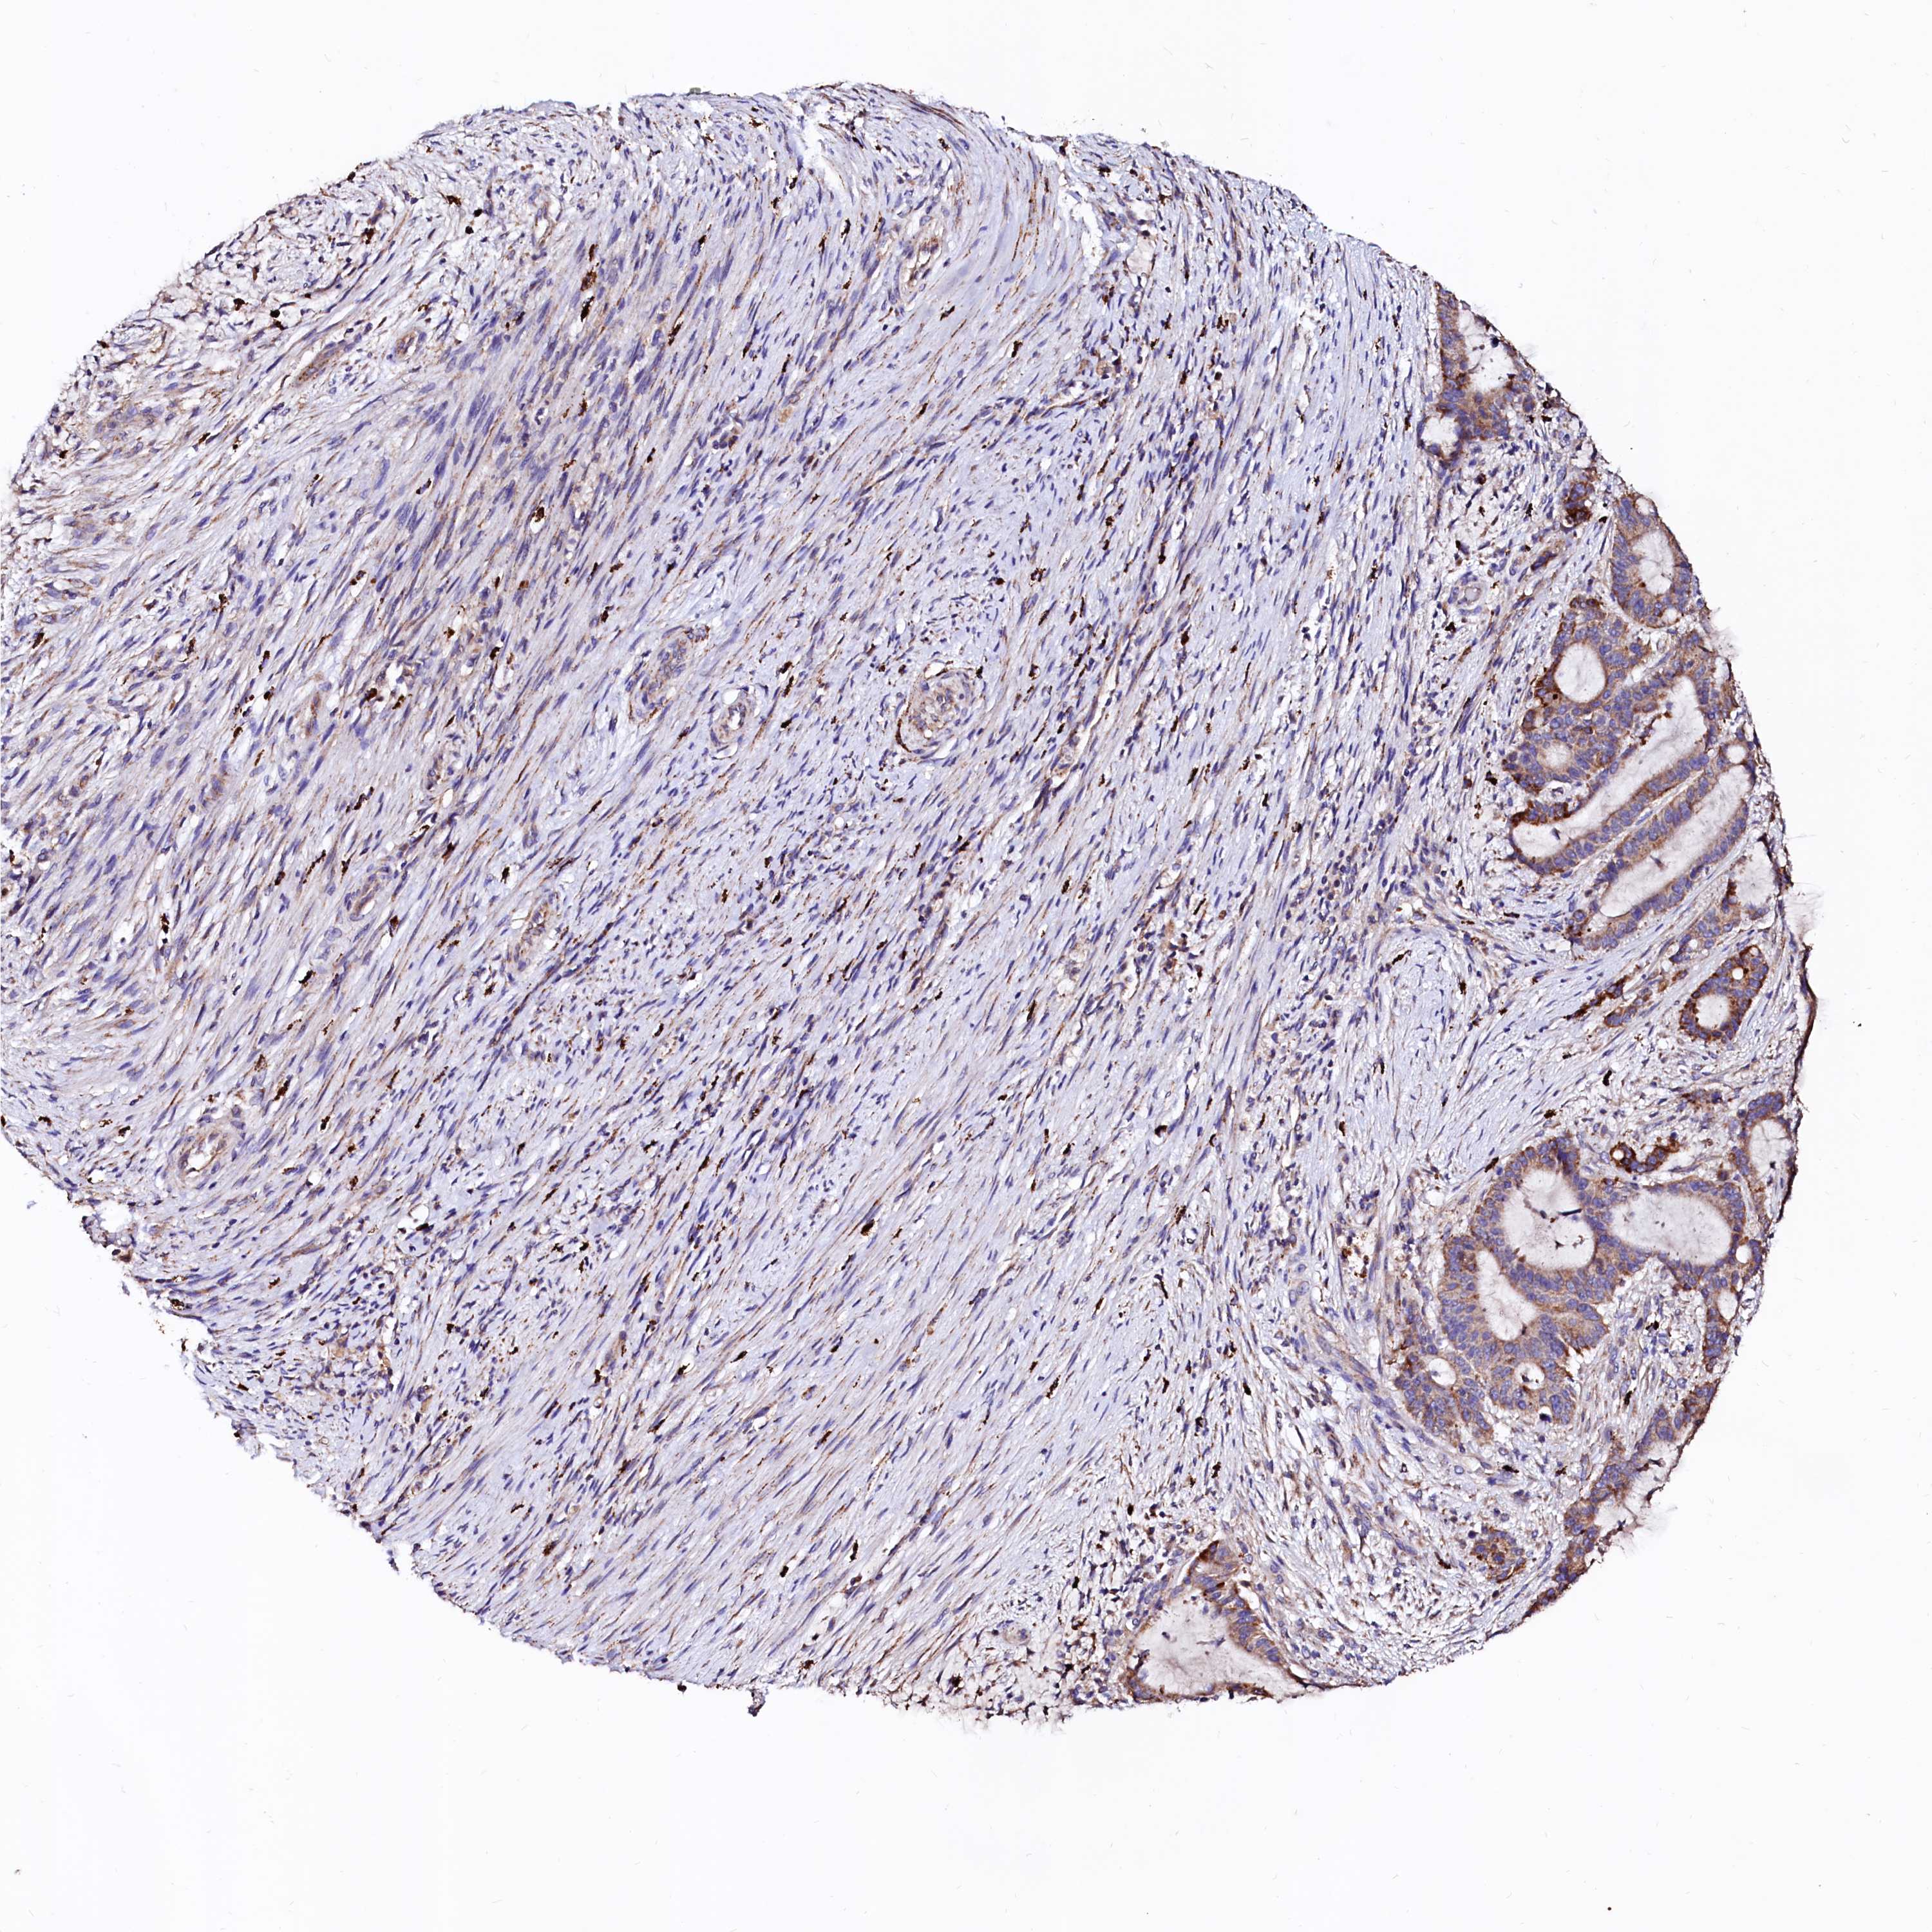

LIVER CANCER - Protein expressioni

A mouse-over function shows sample information and annotation data. Click on an image to view it in a full screen mode. Samples can be filtered based on level of antibody staining by selecting one or several of the following categories: high, medium, low and not detected. The assay and annotation is described here.

Note that samples used for immunohistochemistry by the Human Protein Atlas do not correspond to samples in the TCGA dataset.

Antibody stainingi

Antibody staining in the annotated cell types in the current human tissue is reported as not detected, low, medium, or high, based on conventional immunohistochemistry profiling in selected tissues. This score is based on the combination of the staining intensity and fraction of stained cells.

Each image is clickable and will lead to virtual microscopy that enables deeper exploration of all samples and also displays staining intensity scores, fraction scores and subcellular localization as well as patient and tissue information for each sample.

Antibody HPA002328

Antibody CAB037200

Staining

High

Medium

Low

Not detected

Intensity

Strong

Moderate

Weak

Negative

Quantity

>75%

75%-25%

<25%

None

Location

Nuclear

Cytoplasmic/membranous

Cytoplasmic/membranous,nuclear

Carcinoma, Hepatocellular, NOS

Cholangiocarcinoma